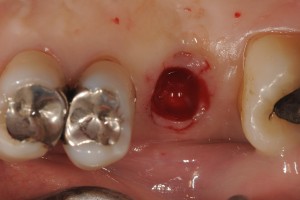

埋入部位をパンチアウトしています。